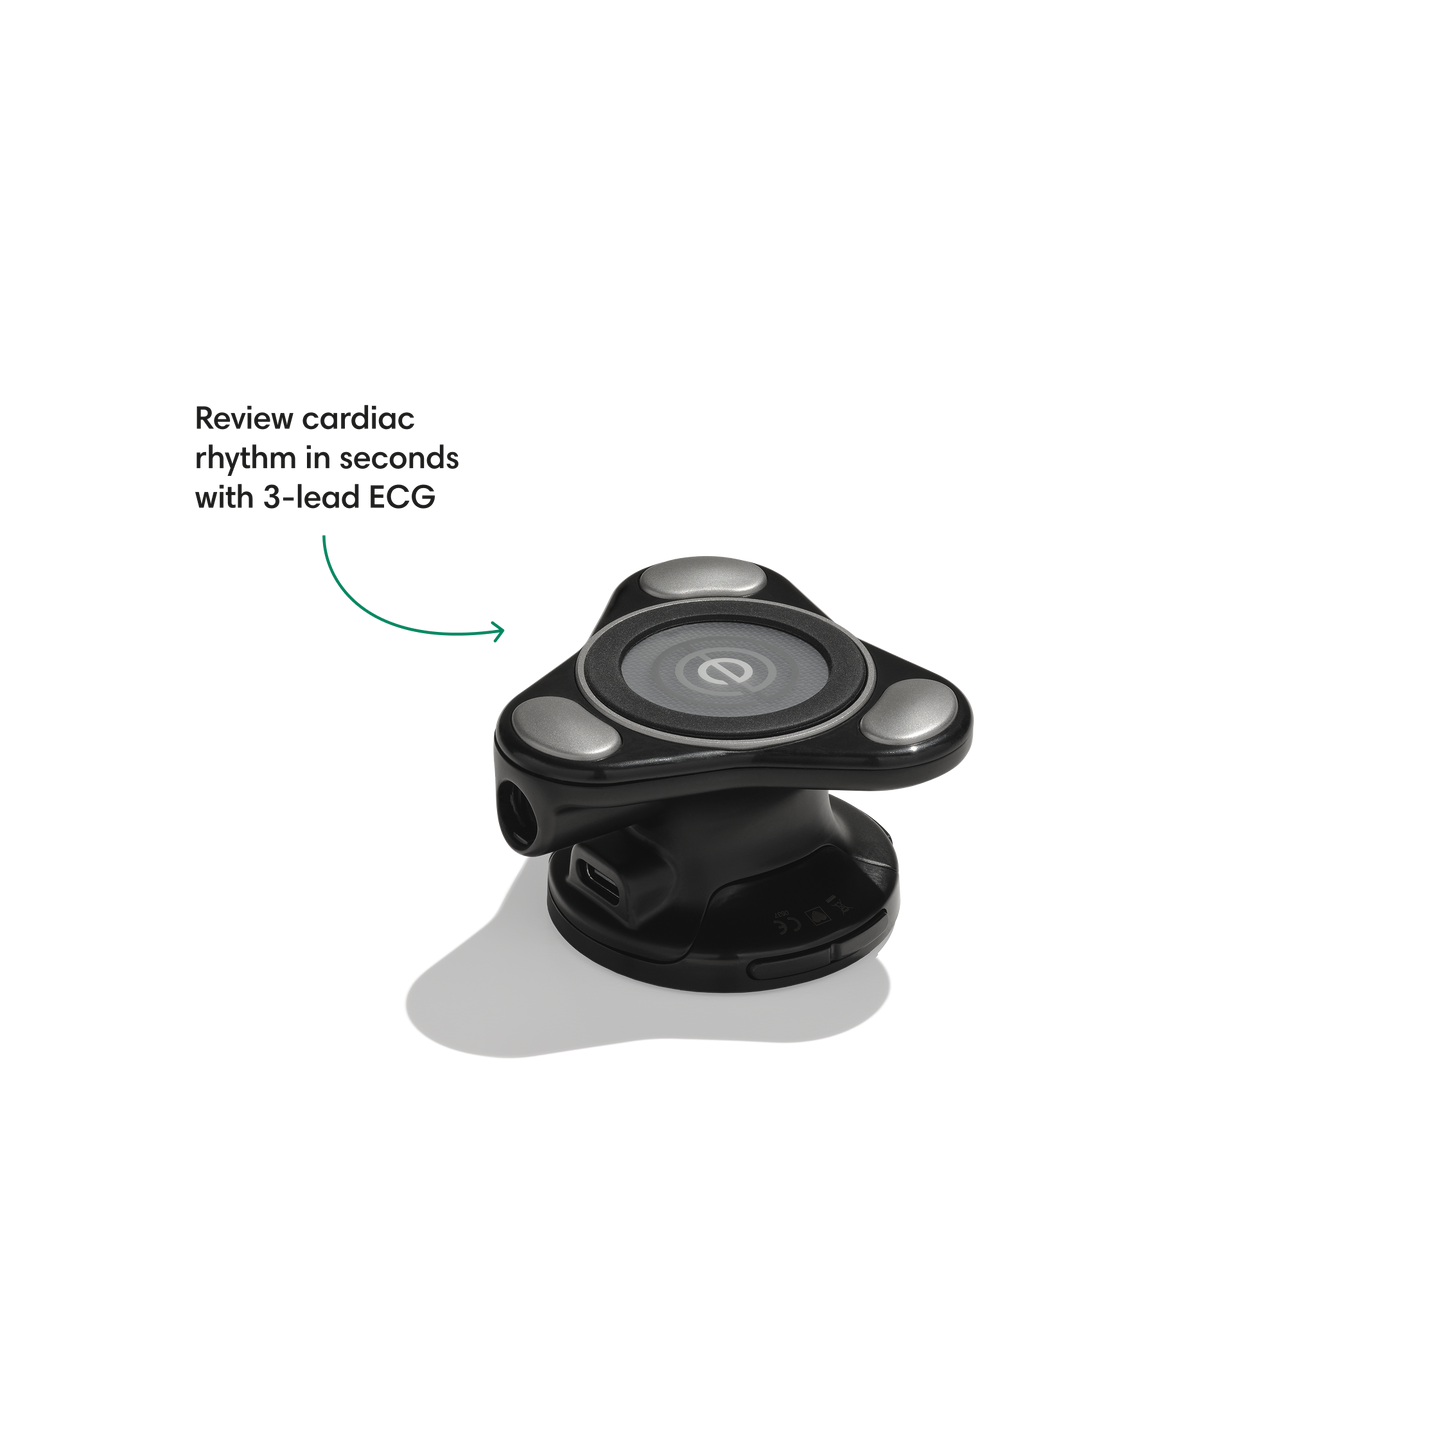

Go beyond sound alone.

For the first time ever, measure heart rate, visualize 3-lead ECG, and see detection results — right on a built-in, full-color display.